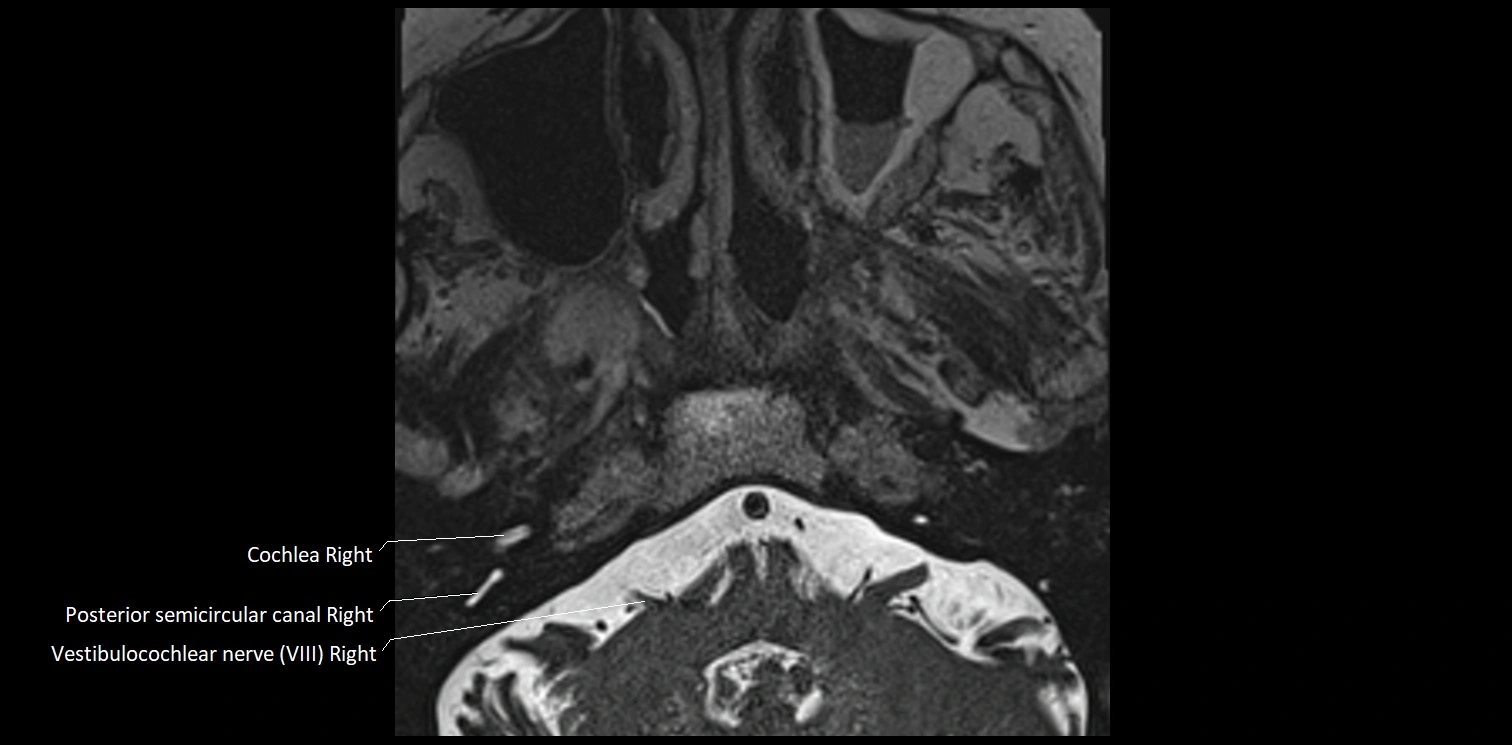

MRI Appearance

• The abducens nerve is a small, thin, linear structure

• Best visualized on high-resolution T2-weighted 3D MRI sequences (e.g., FIESTA or CISS)

• Seen as a hypointense (dark) line running from the brainstem at the pontomedullary junction, traversing the prepontine cistern, and entering Dorello’s canal under the petrosphenoidal ligament, then into the cavernous sinus, and finally the orbit

• May be challenging to visualize in standard MRI due to its small size

• Pathology may be inferred by absence, displacement, or enhancement of the nerve